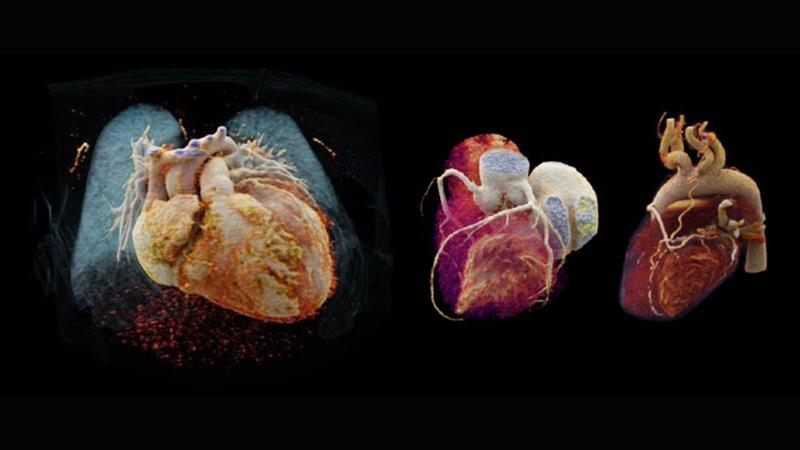

Courtesy of University Hospital Erlangen, Erlangen, Germany

Adaptive Cardio Spiral

Multiple bypass assessment听

- Robust cardiac imaging with myExam Companion听

- Enhanced delineation of soft and hard plaque thanks to ADMIRE iterative reconstruction听

- Cinematic VRT听

- 0.8 mm MPRs used for reconstructions听

- Curved MPR of LAD